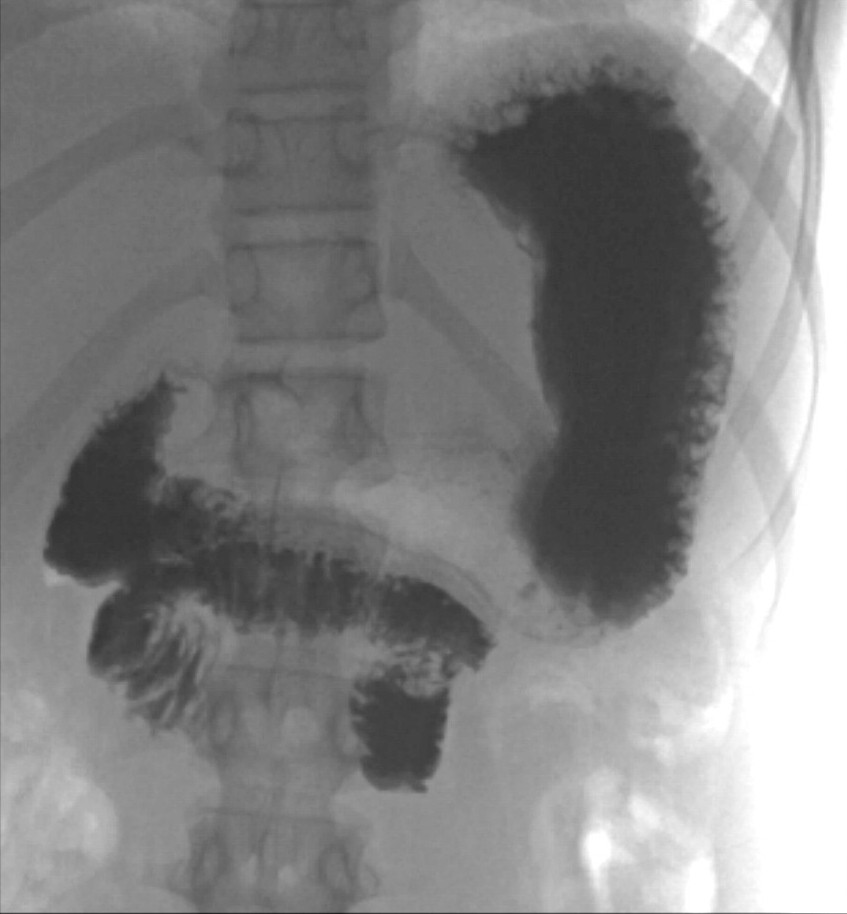

Gjennom helgen ble jenta observert. Hun hadde bedre allmenntilstand, lite magesmerter og ingen episoder med oppkast. Elektrolyttnivået ble raskt normalisert etter påbegynt væskebehandling. Mandag formiddag ble det gjort ultralydkontroll av en erfaren barneradiolog som bekreftet funn av virvellignende rotasjon (figur 1 og 2) og som mistenkte ledsagende volvulus (tarmslyng som følge av at et tarmsegment vris rundt sin egen akse). Diagnosen ble bekreftet med røntgen øsofagus, ventrikkel og duodenum som viste kontrastpassasje til proksimale tynntarm, men ikke videre (figur 3). Overgangen mellom duodenum og tynntarm lå like til venstre for midtlinjen, kaudalt for nivå med bulbus duodeni, noe som indikerte malrotasjon med volvulus. Man hadde omsider funnet forklaringen på pasientens langvarige plager (figur 4).

Ved volvulus vil røntgen av øsofagus, ventrikkel og duodenum vise en obstruksjon, ofte med et «korketrekkerforløp» av duodenum og manglende fylning videre. Ved mistanke om volvulus bør det gis vannløselig kontrast ved røntgen, da det kan bli behov for tarmreseksjon, og lekkasje av kontrast kan forekomme peroperativt.